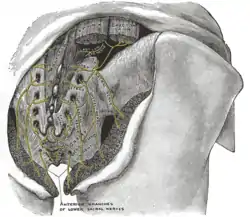

Nervous system The posterior divisions of the sacral nerves.

The posterior divisions of the sacral nerves. Plan of lumbar plexus.